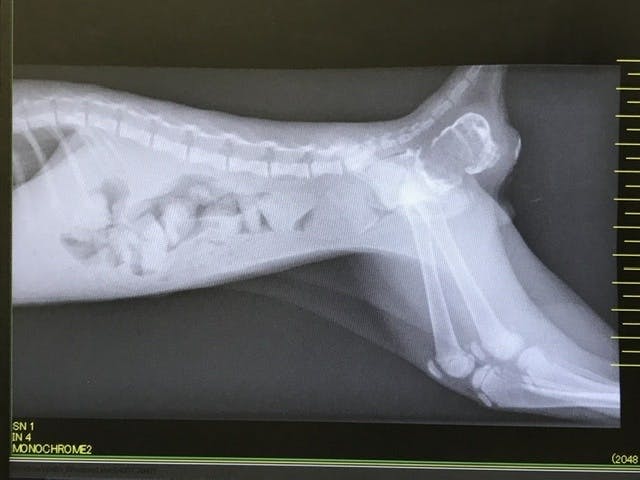

シノちゃんは動物医療センターで「先天性の鎖肛」という病気と診断され、至急、手術を受けました。

子猫の鎖肛の手術は一度では完治せず、再発の可能性がとても高いそうです。

子猫は回復力が高いため、直腸と肛門を広げる手術をしても元の状態(お尻の穴が小さくなる・直腸が狭くなる)に戻ってしまうことが多いそうです。2〜4回の再手術が多いとのことです。

シノちゃんはお尻の穴が小さいため、排便が難しく、便が腸に溜まっており、お医者さんからは、手術をしなければ、3ヶ月はもたないと言われ、シノちゃんは死を待っている状況です。

2020年6月15日 動物医療センターで鎖肛と診断・緊急手術

2020年6月29日 抜糸処置・再発の兆しあり、再度手術を要すると診断を受ける

2020年7月30日 2度目の手術。

2020年8月7日 便が全く出なくなり、浣腸処置。

2020年8月11日 3回目の手術。

現在、術後経過観察中。